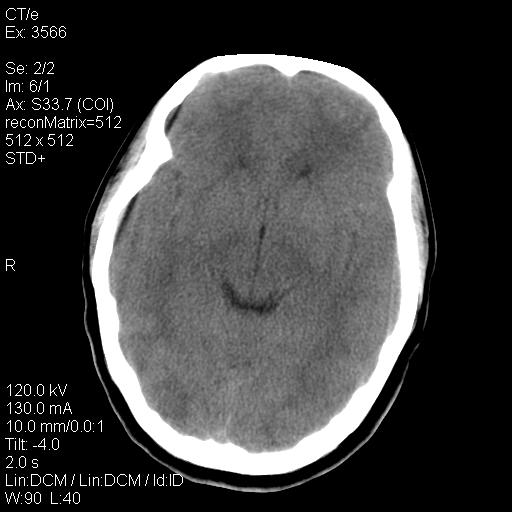

标题: CT9947:女,20岁,妊娠9个月,突然癫痫症状 [打印本页]

标题: CT9947:女,20岁,妊娠9个月,突然癫痫症状

双侧脑白质缺血缺氧性改变,并高度可疑“蛛网膜下腔出血”。

后可复性脑病,

考虑 妊娠子痫或妊高征

双侧脑白质缺血缺氧性改变.

考虑先兆子痫\\子痫致he,建议mri除外有无合并静脉窦血栓形成.

考虑pres

的确应该考虑可逆性后部脑病综合症--pres。感谢天南地北老师的指引,又学了一招儿,开心,呵呵!

考虑可逆性后部脑病综合症

支持pres